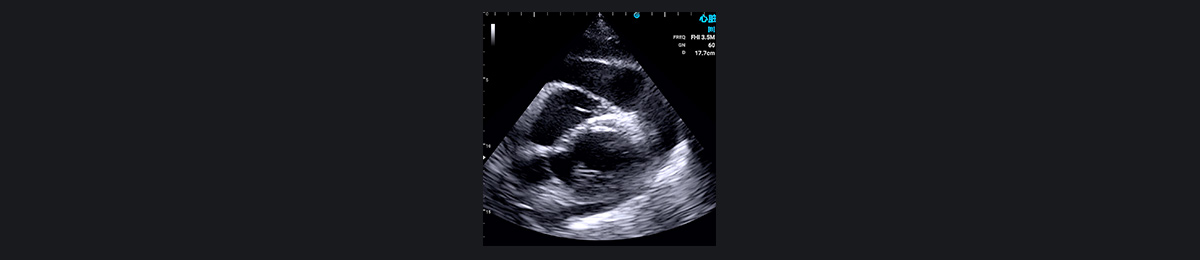

¶ÔÓÚ¼±ÐÔÐØÍ´µÈΣ¼°ÉúÃüµÄÐØÍ´×ÛºÏÕ÷£¬SonoEye ¿ÉÒÔÌṩ¹Ø¼üµÄÐÄÔàÕï¶Ï£¬ÉîÈëÁ˽â°êĤÎÊÌâ¡¢Ðİü¼²²¡»òÔ·¢ÐÔÐļ¡×´¿ö¡£Ëü¶ÔÓÚÆÀ¹ÀÒÉËÆ¼±ÐÔÐ£ËÀ»¼Õߣ¨ÐĵçͼȷÈÏǰ£©¡¢ÑªÁ÷¶¯Á¦Ñ§²»Îȶ¨»¼ÕßÒÔ¼°ÑÏÖØ·Î˨Èû»¼Õ߷dz£ÓмÛÖµ¡£Ê¹Óà SonoEye ½øÐÐ×ۺϳ¬ÉùÐĶ¯Í¼¼ì²é¿ÉÒÔÆÀ¹ÀÖ÷¶¯Âö¼Ð²ãµÄ·¶Î§ºÍ²¢·¢Ö¢£¬Ñ°ÕÒÐİü»òÐØÇ»»ýÒº£¬²¢²âÁ¿Ö÷¶¯Âö¸ù²¿µÄÖ±¾¶¡£

¶þ¼â°êÏÁÕ¡¢×óÐÄ·¿Ö×Áö¡¢×óÐÄË¥½ß¡¢·ÊºñÐÔÐ¡¡¢Ðİü»ýÒº»òËõÕÐÔÐİüÑ×ÒÔ¼°ÑÏÖØµÄ·Î˨ÈûµÈÇé¿ö¾ù¿Éµ¼ÖºôÎü¶Ì´Ù»òºôÎüÀ§ÄÑ¡£Ê¹Óà SonoEye ÊÖ³Öʽ³¬Éù²¨¿ÉÒÔÓÐЧÕï¶ÏÕâЩ²¡Ö¢¡£

Ðİü»ýÒº